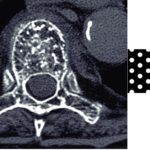

Image Quiz 9

Popular Answer may not imply right answer. Follow our twitter handle for the right answer, https://bit.ly/3CoX2vB